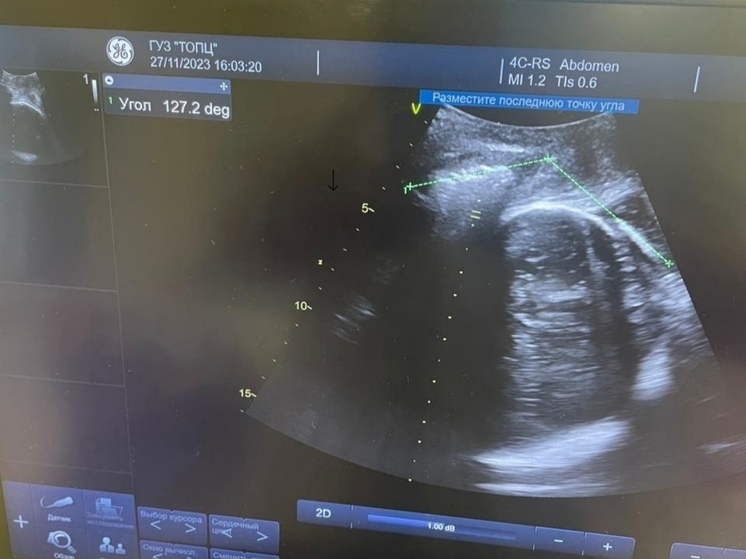

Фото: Тульский областной перинатальный центр

В Тульском областном перинатальном центре продолжают внедрять новые методы и технологии. Теперь прямо во время родов женщинам могут сделать УЗИ. Такой способ позволит в режиме реального времени точно определить положение головки плода и её движение в потужном периоде.

Новый метод ведения беременности позволит избежать рисков. Например, врач сможет определить способ родить – естественно или кесарево сечение. Точность приближается к 100%, хотя ранее составляла всего 50-60%.